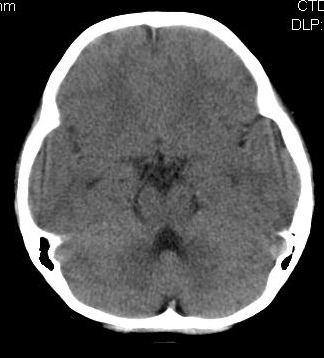

女,10岁,智力发育不良,既往史无特殊。

脑裂畸形,灰质异位